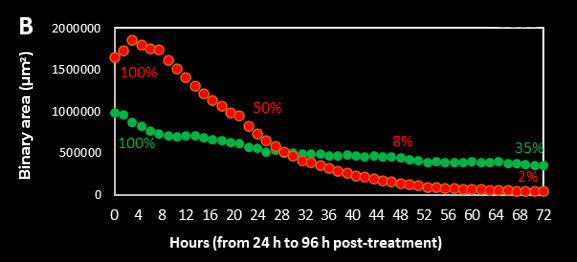

On the Z-sum intensity projection images created along the movie, the area covered by both AD-MSCs TRAIL (green fluorescence) and A673 tumor cells (red fluorescence) were quantified by using binary images through the identification of regions of interest (ROIs) around fluorescent cells (NIKON NIS Elements software tool). A representative movie is shown in Figure 4A. In order to evaluate the killing anti-cancer therapy effect induced by AD-MSCs TRAIL to A673 tumour cells, the total area covered by cells was measured and quantified over time (Figure 4B). As shown in the graph curve, red covered area decreases firstly to 50% after 48 h post-treatment, furtherly reducing to 8% at 72 h post-treatment and then to 2% at 96 h post-treatment. The observed trend suggests that the pro-apoptotic process was effectively activated being entirely monitored in the considered time frame. On the contrary, AD-MSCs TRAIL maintain a good area coverage over time. The slight decrease to 35% at 96 h post-treatment may be explained by the capability of cells to migrate towards still-viable tumor cells, considering also their intense activity observed in Figure 3 movie.

Figure 4. Montage and binary area measurements along the movie. (A) A representative video of the two binary areas (green and red). (B) The total areas covered by cells from the first (24 h post-treatment) up to the last time frame (96 h post-treatment) were measured and quantified by using the following calculation: (% = (binary area (µm2)each time point*100)/ binary area (µm2)starting point).